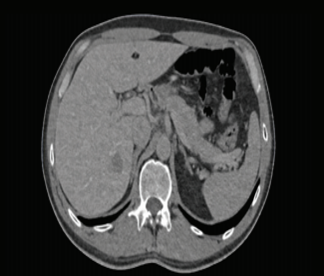

확률적인 접근은 신호처리 분야에서 효과적인 방법이다. 그 이유는 신호측정 장비 혹은 영상촬영 장비를 통해서 얻어진 신호 정보에는 필연적으로 노이즈를 포함하게 되는데, 확률적인 접근은 이런 노이즈를 복잡한 물리적인 해석없이 간단한 가정을 통해서 평균적인 처리를 가능하게 하기 때문이다.